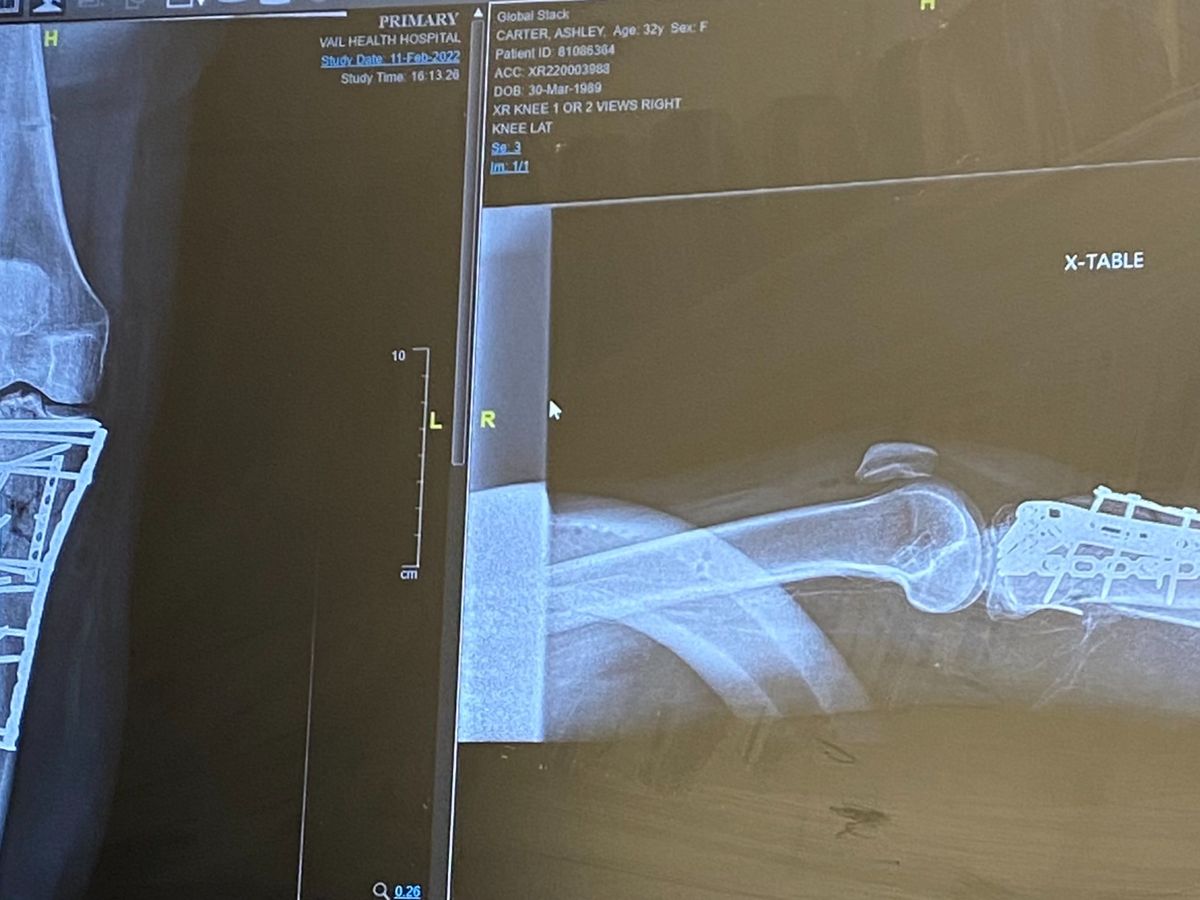

Hi, my name is Ashley Carter and I am raising funds to help cover the cost of a hardware removal surgery scheduled for May 12th. In February of last year, I shattered my tib/fib in a ski accident and needed a good amount of hardware put in (4 plates and 20sih screws). I had 2 surgeries and spent 10 days in the hospital. After more than a year of recovery, physical therapy, seeing a psychologist, and the support of my friends & family it is time to have all the hardware removed. While the surgery is not an emergency need it is necessary to relieve the daily pain, discomfort, and movement restrictions from my leg/knee. Unlike the first emergency surgery and the second surgery to

put in all the hardware, I am required to pay my part before they will perform the surgery. If you've met me you know I thrive when I get to spend my days in the outdoors, playing sports, and dancing as much as possible. This surgery will help me continue the forward motion of recovery and get back to enjoying all the parts of life I have been missing. Thank you in advance for any and all support! Here is a video that shows the extent of the original injury- injury video and here is a video of the year journey in a nutshell: